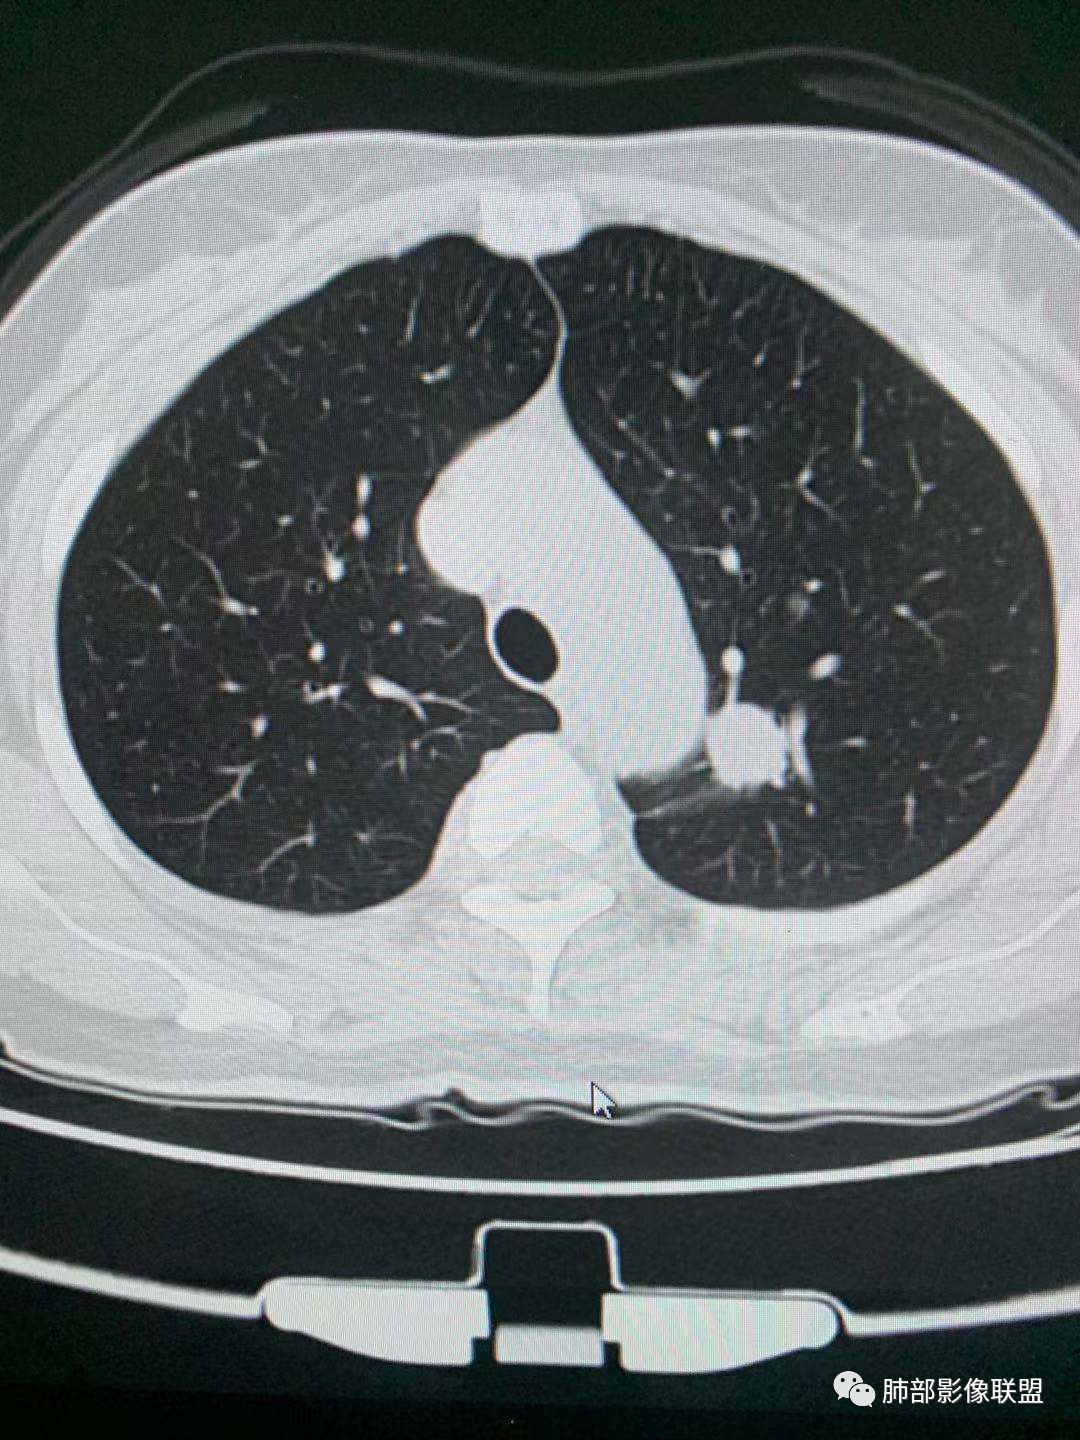

一.尖后段高密度大结节:

1.左肺上叶尖后段较大类圆形实性密度结节影,密度均匀,中等程度强化。

2.实性密度区边缘相当清楚,表面欠光整,偶见毛刺、棘突和旁出血管结构,未见典型的深分叶及邻近胸膜凹陷。

3.可疑支气管进入受阻。可惜缺乏连贯图像或冠矢状位以资判断。

4.病灶与胸膜之间有连线,邻近段支气管及肺血管整体后移,提示病灶还是有一定收缩性。

如上,单就这实性结节,硬化性肺细胞瘤(PSP)和腺癌似乎都能够解释,形态太规整了一些。

5.病灶周围见边界清楚的磨玻璃影,有点醒目,有点意外!

这是无论如何不能忽视的征象!

这点强烈提示,要么整个病灶恶性(腺癌),要么良性病灶旁滋生恶性病灶。

两年前左上肺的病灶什么位置,什么模样,是否相关?我们不得而知。

二.左肺上叶前段磨玻璃结节:

该结节较大,边界清楚,小叶间隔阻挡特征相当明显,微浸润腺癌的诊断几乎没有争议!

三.右肺上叶胸膜下结节及左肺上叶血管旁结节,尽管都是磨玻璃密度,但都比较小且边缘特征不明显,恶性征象未显露,处置并无特殊,定期复查!